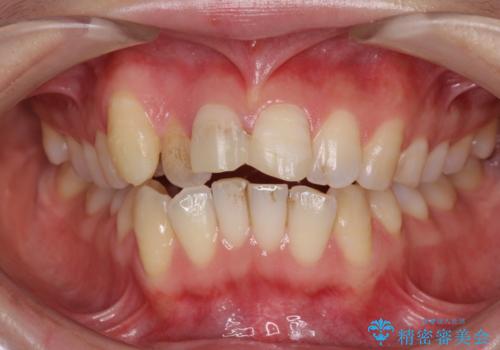

転んで前歯が欠けた 折れた前歯をきっかけに矯正治療で歯列をきれいに整える

- 転倒により前歯の一部が欠けてしまったとのことで来院された患者様です。

元々歯並びが気になっていたとのことで、前歯の治療を行うことを契機に矯正治療も行うこととしました。